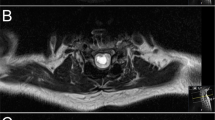

The optimal therapeutic strategy in patients with spinal cord tethering with or without syringomyelia remains currently a challenge10. However, since several years a growing body of evidence points towards surgical untethering of the spinal cord in symptomatic cases14,15. In this investigation all patients received spinal cord untethering and expansion duraplasty with or without syrinx shunting (Fig. 3) as described by Falci et al.5. The postoperative result of surgical success of untethering and expansion duraplasty was subsequently documented by regular follow up MRI of the spinal axis. Interestingly and in line with the study of Gauillamet et al.16, our revision rate in patients with extensive arachnoiditis (> 3 vertebral segments) was significantly higher than in patients with focal arachnoiditis while the need for implantation of a shunt did not affect the rate of surgical revisions. Due to the results of this investigation we are able to further strengthen the level of evidence for recommendation of untethering and expansion duraplasty including cyst shunting (when indicated) with a mean follow-up of 8.1 years after surgery. As such we are in line with one of the largest outcome studies regarding posttraumatic spinal cord tethering and syringomyelia with over 10 years of follow-up using a similar and consistent surgical approach5 including an investigation demonstrating good long-term results of a surgical strategy with progressive neurological loss in AIS grade A, B, and E injuries9. Of note, postsurgical imaging significantly correlated with improvement of clinical symptoms by a decrease of tethering and collapse of the respective syrinx. Interestingly and on the other hand, a decrease of spinal cord tethering and the collapse of the syrinx in imaging goes not necessarily along with an improvement of but also with an arrest of further deterioration of clinical symptoms. As such, besides the impairment of CSF flow and subsequently conductivity of the spinal cord, the SCI itself plays a critical role in sustaining clinical symptomatology, particularly in a chronic setting of persistent myelopathy. This adheres with a study from Edgar and colleagues who claimed an 87% improvement if untethering surgery is performed within 3 months of onset of clinical symptoms17. Thus, a timely surgical intervention in symptomatic spinal cord tethering and syringomyelia helps to omit persistent damage to the spinal cord due to impairment of CSF flow and as such progressive myelopathy. Of note, a promising alternative to untethering and expansion duraplasty has recently been proposed by spine column shortening18. Here, the abnormal stretch on the spinal cord due to cord tethering is indirectly treated by a shortening osteotomy, in particular in recurrent tethering or complex cases19, and as such might carry less procedural risk as in untethering. However, operation time and blood loss are significantly higher in column shortening osteotomies so that the indication for such an invasive procedure has to be placed carefully.

Posttraumatic spinal cord tethering and syringomyelia. (A) Midline durotomy is performed with exposure of spinal cord tethering (hypertrophic arachnoid web with scarring aspect and adhesions to the dural sack). (B) Posterolateral resection of scarred arachnoid web is conducted under microscopic conditions (lysis of the arachnoid tissue). (C) After the completion of the lysis of the posterolateral aspect of the spinal cord, an expansion duraplasty is integrated by continuous and non-resorbable suture and attached to the surrounding tissue or instrumentation material in order to persistently expand the intradural space. (D) Intraoperative ultrasound demonstrating the syringomyelia (and spinal cord tethering) is used for intraoperative guidance and quality control. Pre and postoperative magnetic resonance imaging (MRI) show spinal cord tethering and syringomyelia before surgery (E) and after untethering and expansion duraplasty (F). Note the subtotal collapse of the syringomyelia with persistent augmentation of the intradural space due to expansion duraplasty in panel (F).